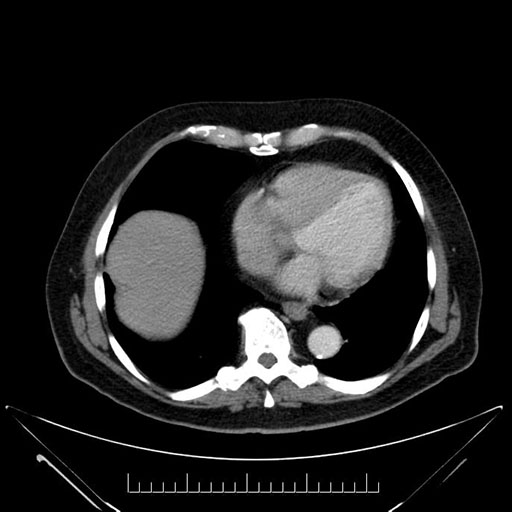

Axial - 3 months prior

Axial - stented

Coronal - stented